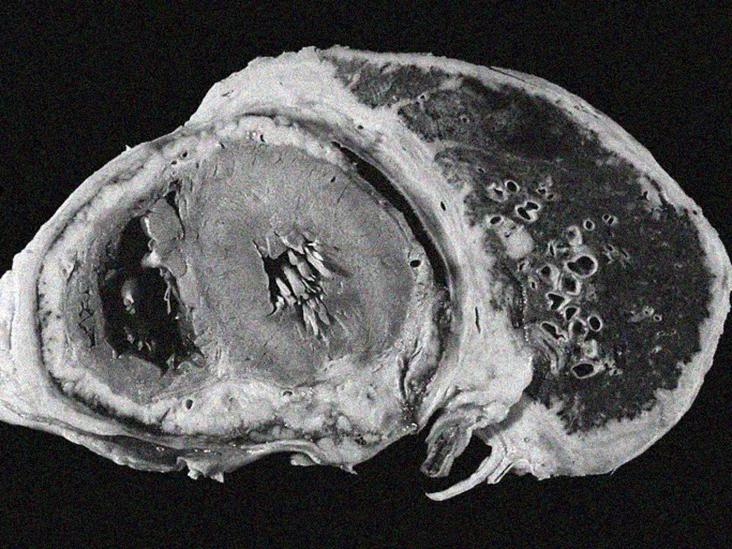

El Cáncer de Pulmón en Radiografías: Una Imagen Compleja

El cáncer de pulmón se presenta de diferentes maneras en una radiografía, dependiendo de su tipo, etapa y ubicación. Las exploraciones por imágenes, como las radiografías de tórax, son herramientas esenciales para el diagnóstico, mostrando la ubicación, gravedad e incluso, en algunos casos, el tipo de cáncer. Interpretar estas imágenes requiere la experiencia de profesionales médicos.

Tipos de Cáncer de Pulmón

Cáncer de Pulmón de Células Pequeñas (CPCP)

El CPCP se suele asociar con el tabaquismo, aunque otros factores como la exposición al asbesto y la radiación también aumentan el riesgo. En radiografías, estos tumores suelen aparecer como masas blancas ubicadas hacia el centro de los pulmones. La estadificación (limitada o extendida) influye significativamente en el pronóstico.

Características en Radiografías

La apariencia de los diferentes tipos de cáncer de pulmón en una radiografía varía. Algunos pueden presentarse como masas bien definidas, mientras que otros pueden mostrar patrones difusos o infiltrados. La presencia de líquido pleural o engrosamiento pleural también puede ser indicativa de ciertos tipos de cáncer de pulmón o metástasis. El tamaño y la ubicación del tumor son importantes para la estadificación y el plan de tratamiento.